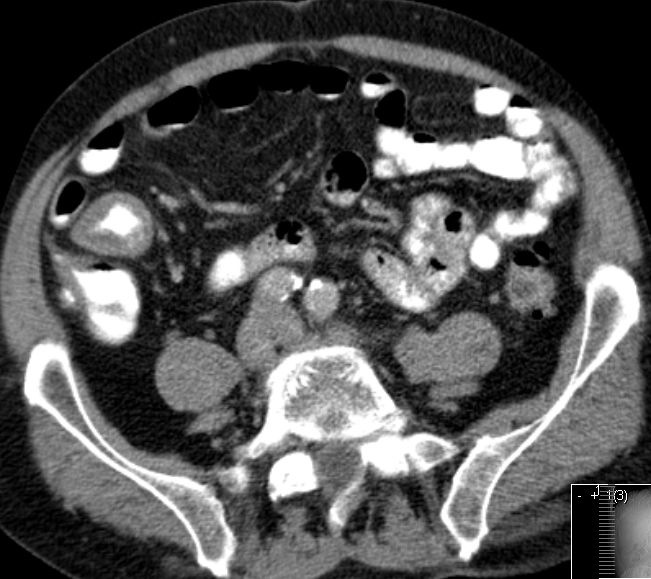

| Beispiele bildgebender Diagnostik von primären Colonkarzinomen | Zökum |

| Beispiele bildgebender Diagnostik von lokalen Metastasen | Lymphknotenmetastasen![]() |

mesenteriale Metastasierung |

peritoneale Metastasierung | |